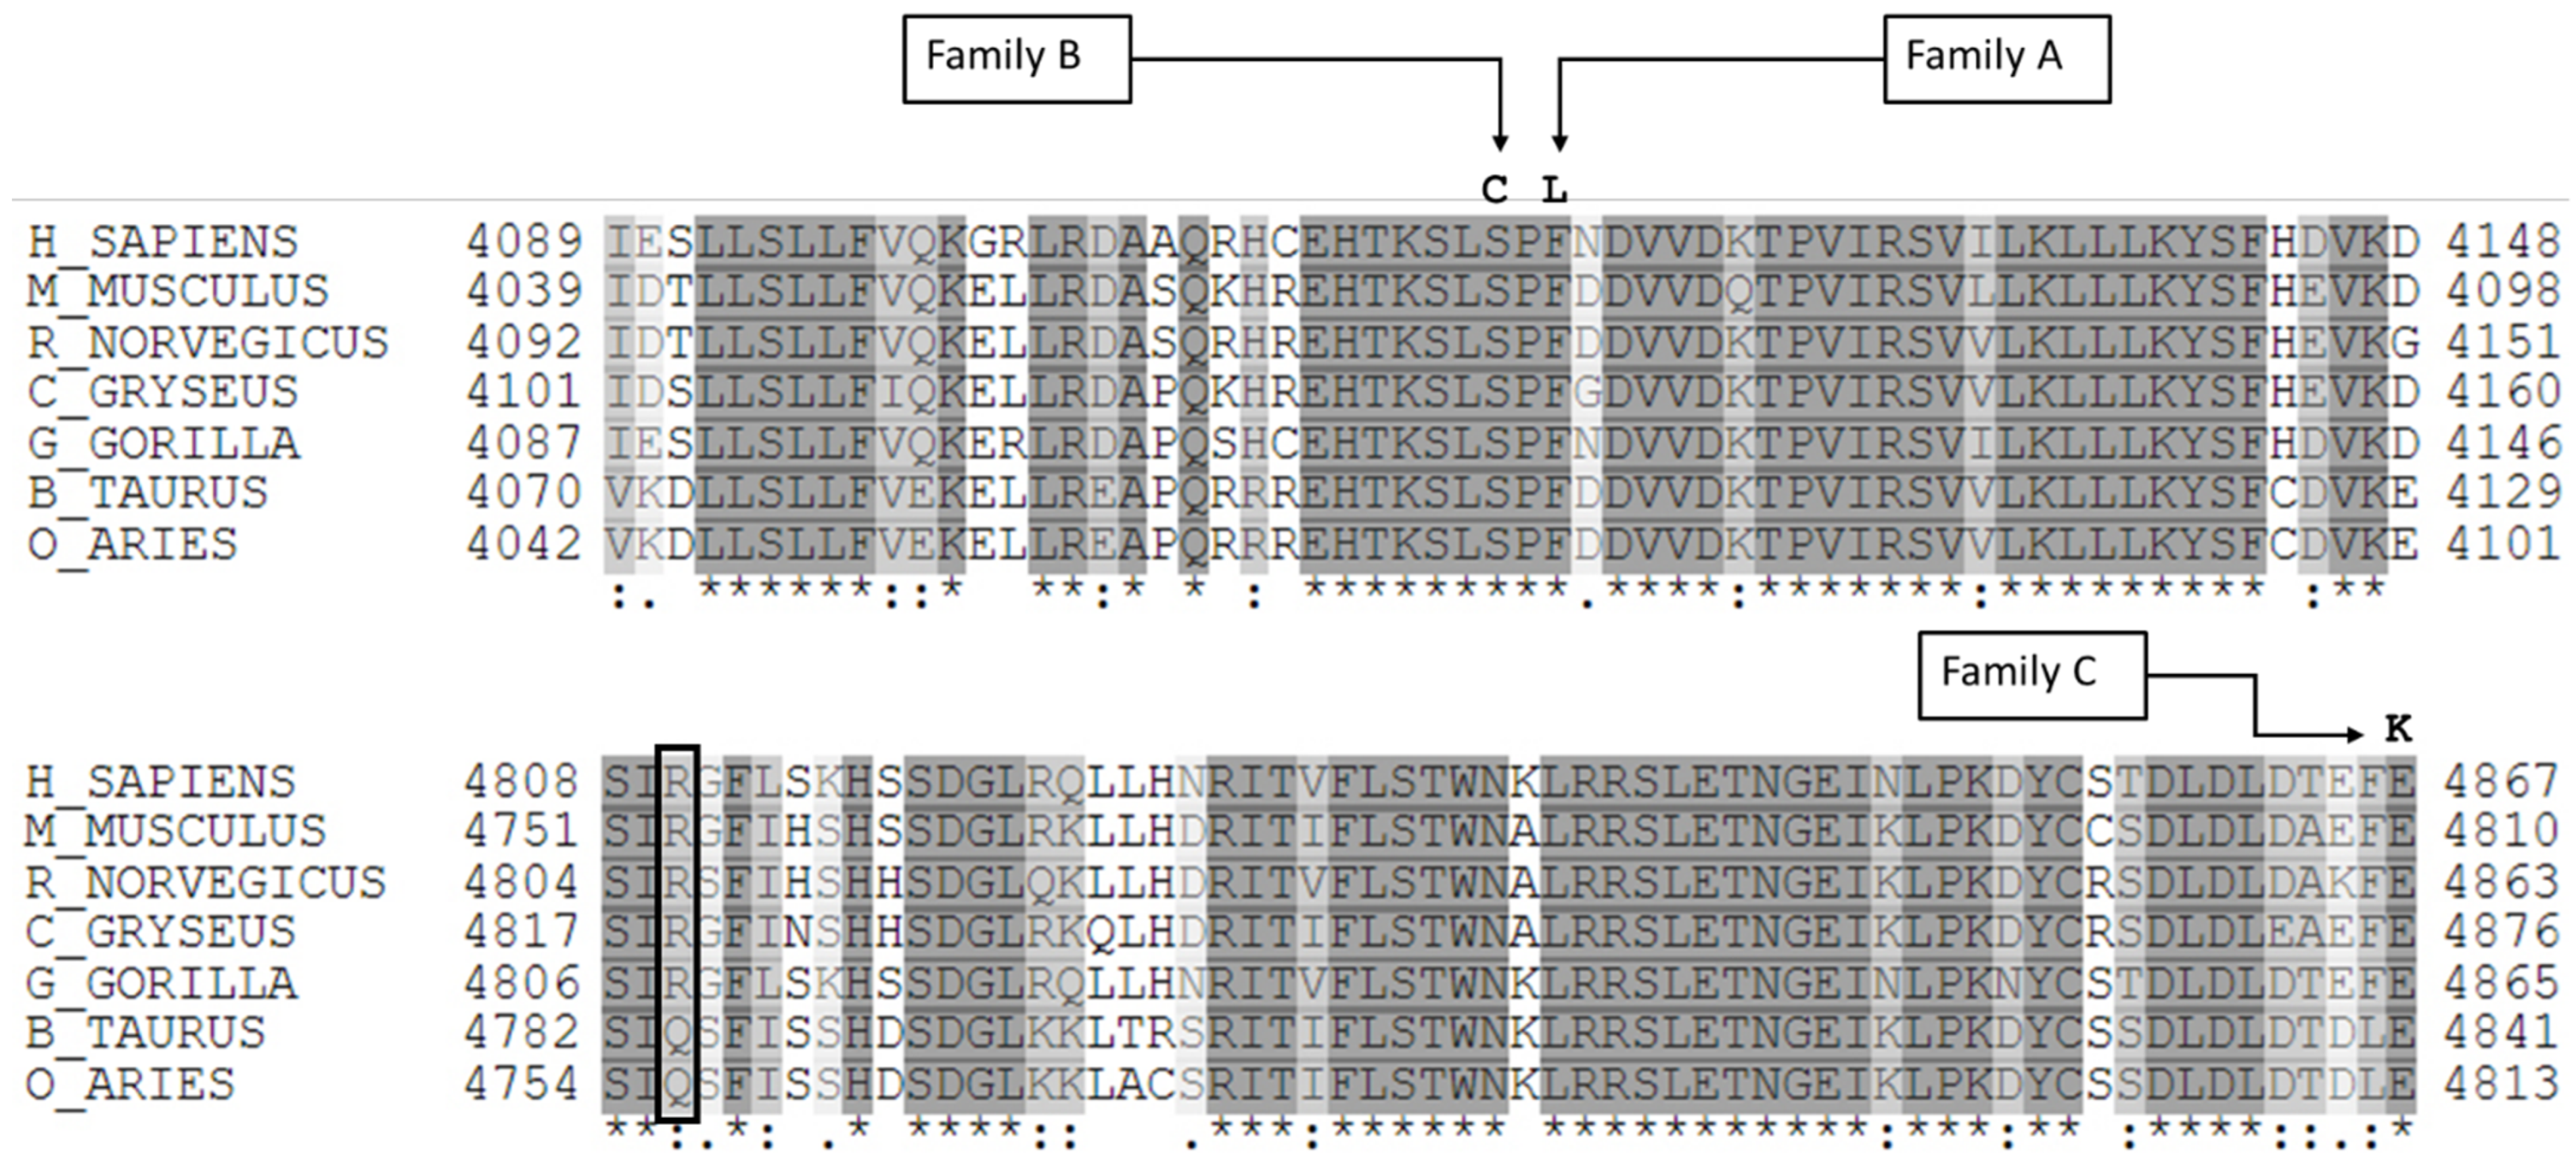

2.4. Molecular Diagnosis